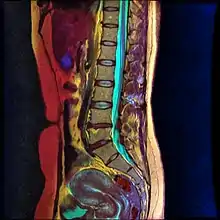

There are multiple posterior percutaneous approaches, but no clinical evidence suggests that any one technique is more efficient than the rest. The posterior approaches generally utilize two needles, one at each side of the L1 vertebral body pointing towards the T12 vertebral body.[3]

Lumbar sympathetic neurolysis is performed between the L1-L4 vertebrae with separate injections at each vertebra junction. The chemicals used for neurolysis of the nerves cause destructive fibrosis and cause a disruption of the sympathetic ganglia. The vasomotor tone is decreased in the area affected by the neurolysis, which in addition to arteriovenous shunting, create a light pink appearance within the affected area. Lumbar sympathetic neurolysis alters the ischemic rest pain transmission by changing norepinephrine and catecholamine levels or by disturbing afferent fibers. This procedure is mainly used only when other feasible approaches to pain management are unable to be used.[6]

Lumbar sympathetic neurolysis is performed by using absolute alcohol, but other chemicals such as phenol, or other techniques such as radiofrequency or laser ablation have been studied. To aid in the procedure, fluoroscopy or CT guidance is used. Fluoroscopic guidance is the most frequent, giving better real-time monitoring of the needle. The general technique of administering lumbar sympathetic neurolysis involves using three separate needles rather than one because it allows for better longitudinal spread of the chemicals.[6]